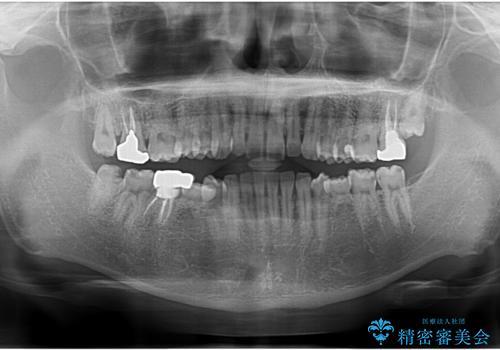

- 口の中を予算の範囲内でできるだけきれいにしたいとのことで来院された患者様です。

矯正治療と虫歯治療を組み合わせてご提案しましたが、ご予算との兼ね合いで虫歯治療のみを行うこととなりました。

奥歯は十分な歯の高さがなかったため、クラウンをかぶせる前に歯周外科治療で歯の高さを出しています。

歯科に通うようになってから磨き残しの状態も改善されていきました。